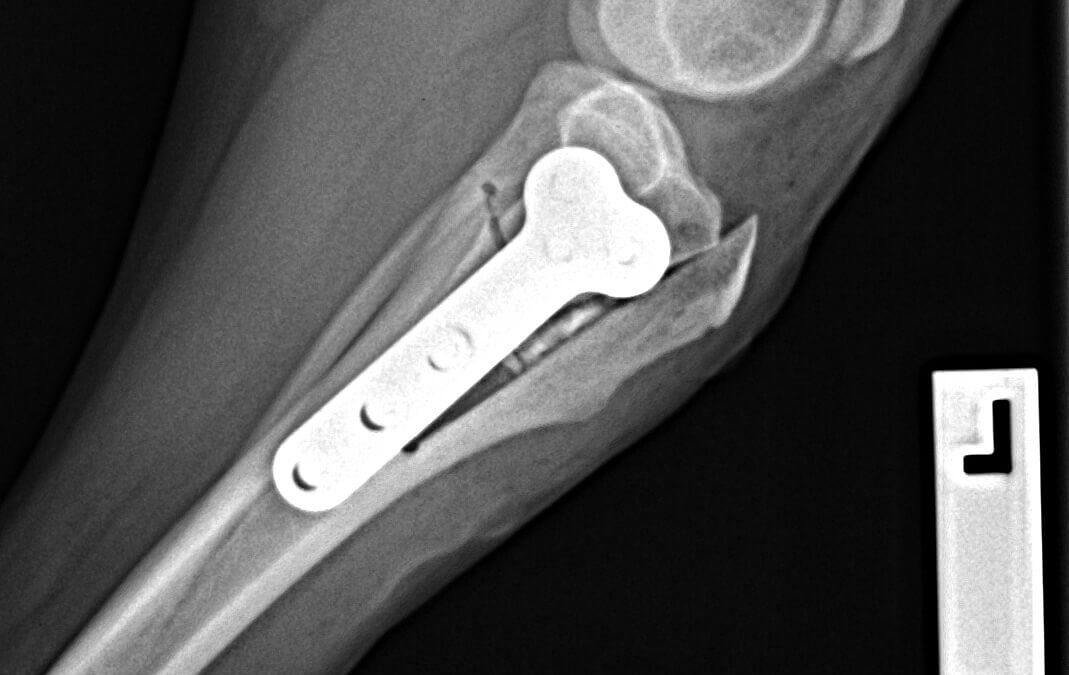

Miles-Houghton-TTO-after-2